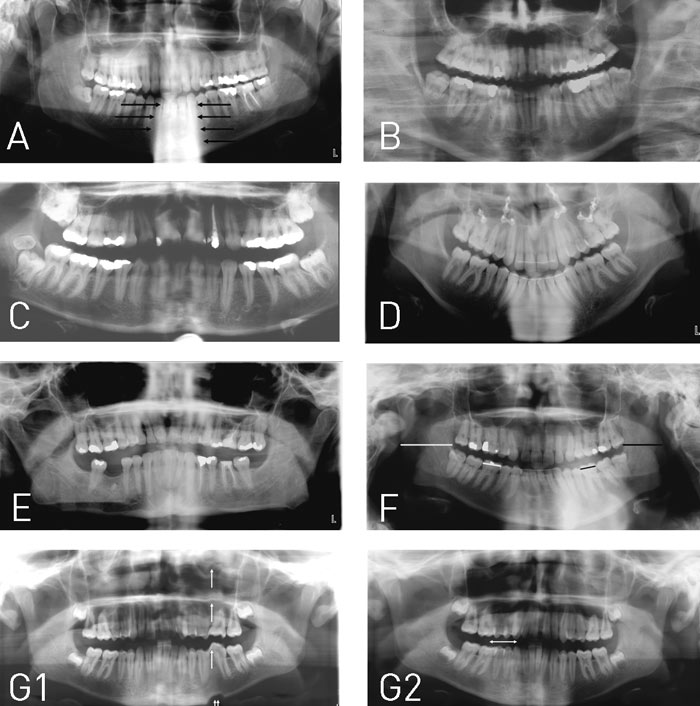

De hyppigste patientpositioneringsfejl fremgår af Fig. 3. Disse fejl i sammenhæng med panoramabilledets generelle begrænsninger, såsom begrænset opløsning (en konventionel panoramafilm har en opløsning på 5 – 6 linjepar pr. mm i modsætning til en intraoral film, som har en opløsning på ca. 20 linjepar pr. mm), stor forstørrelsesgrad (ca. 15 – 70 %, som kan variere inden for det samme billede), hyppige approksimale tandoverlapninger i præmolar-/molarområderne samt overprojektion af blødtvæv, luft og «spøgelsesskygger» (se senere) på relevante kæbe-/tandområder skal tages i betragtning, før panoramaoptagelsen vælges frem for alternative optagelser for radiologisk udredning af et konkret problem.

Fig. 3. De almindeligste patientpositioneringsfejl: A: En ikke udstrakt halshvirvelsøjle vil resultere i en kompakt, radiopak skygge over hagepartiet (pile), således at underkæbens front (inkl. incisiver) fremstår skjult/overprojiceret. B: Anterior placering af patientens incisiver i forhold til apparatets skarphedszone vil resultere i uskarpe og for smalle incisiver. I tillæg vil patientens halshvirvler dominere i billedets sidepartier, hvor de vil overprojicere højre og venstre ramus mandibulae. C: Posterior placering af patientens incisiver i forhold til apparatets skarphedszone vil resultere i uskarpe og for brede incisiver. D: Sænket hage vil resultere i et forholdsvis stort hageparti og en positiv «smileprofil». Et sådant billede vil almindeligvis være karakteriseret af uskarpe underkæbeincisiver og evt. manglende gengivelse af kæbeledskondyllerne, som vil være placeret superiort for billedarealet. E: Løftet hage vil resultere i et billede præget af en negativ «smileprofil». På et sådant billede vil overkæbeincisiverne aftegnes uskarpt, og bagkanterne af rami mandibulares vil ofte mangle inden for billedarealet. F: Roteret position af patientens kæber vil resultere i forstørrelsesvariation mellem højre og venstre sides tænder og kæber. Den side, som patienten roterer næsen imod (her højre side), vil blive gengivet større i horisontal retning (hvide streger) end den modsatte side, som vil gengives formindsket i horisontal retning (sorte streger). G: Patientbevægelse under eksponeringen vil resultere i uskarphed og fortegning. Bevægelse i vertikal retning kan medføre konturspring i basis mandibulae (dobbelt pil) og bølgeformet fortegning af alle strukturer herover (enkelte pile) (Fig. G,1). Bevægelse i horisontal retning medfører uskarphed og evt. dobbelttegning af tænder (pil) (Fig. G,2).